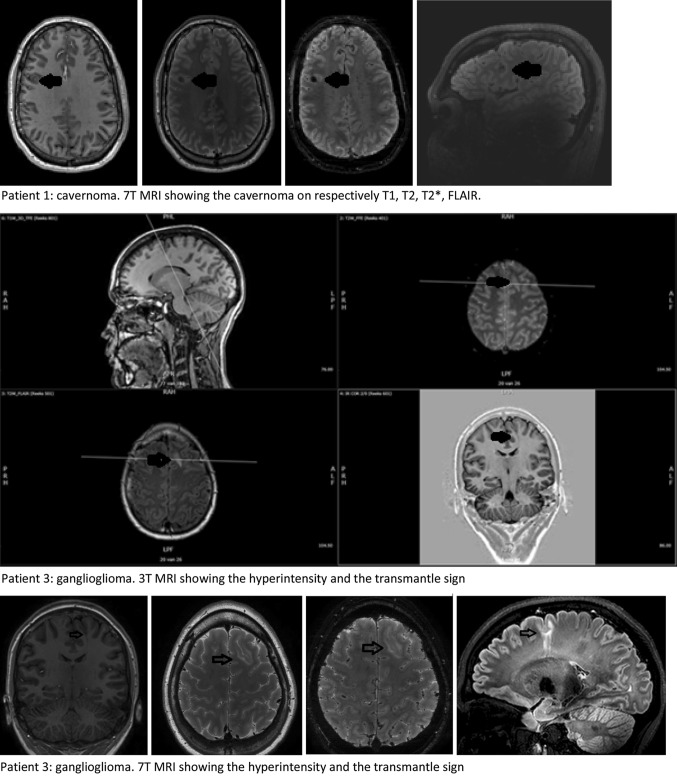

Five of the six included patients that were also evaluated for epilepsy surgery were operated. In patient 3 histopathology showed a ganglioglioma WHO grade 1, patient 8 had FCD type IIIb (frontal infantile desmoplastic ganglioglioma with bordering FCD operated plus parietal FCD that we analysed in this study), patient 9 showed a FCD type IIa and patients 10 and 11 showed a FCD type IIb. The location of the lesion was congruent between MRI and surgical specimen. The 3 and 7 T MRI images of the two patients in whom the diagnosis changed from FCD to, respectively cavernoma and ganglioglioma are shown in Fig. 6.

Fig. 6.

3 and 7 T MRI images of the two patients with changed diagnosis. Each sequence contrasted and angulated individually

The main finding of this study is that all observers agreed that on conventional visual analysis the lesions were easily detected and better detailed with the applied 7 T MRI protocol than on lower field strength. None of the known lesions were missed on the 7 T images. Using a semi-quantitative scale, overall our 7 T MRI protocol tended to be superior to the previously applied 3 T protocol. Statistical significance was reached for 4 out of 14 scored items. In two patients final diagnosis changed from FCD to, respectively cavernoma and gangioglioma.

In one patient, due to the 7 T images diagnosis changed from FCD to cavernoma. There are several explanations possible for this change. First, due to slice thickness in the 3 T images the small hemosiderin deposit could have been located exactly in between two slices, thus escaping detection. Due to the thinner slice thickness of the 7 T images, the hemosiderin is more obvious. The images as depicted in Fig. 6 seem to substantiate this hypothesis. Second, the artefact effect of hemosiderin is more pronounced on 7 T MRI than on 3 T MRI, thereby highlighting the cavernoma more evidently in 7 T MRI. The sequence most sensitive for hemosiderin is SWI (susceptibility weighted imaging). However, in epilepsy the presence of small hemosiderin deposits is of minor relevance and therefore in the initial phase of our study this sequence was not part of our standard epilepsy protocol. This will have probably lowered the sensitivity for the detection of small haemorrhages of the 3 T MRI more than the sensitivity of 7 T MRI. Especially compared to 7 T MRI in which a T2* weighted sequence was part of the protocol. Third, there is a time delay of several months between these 3 and 7 T MRI’s. Although there were no additional clinical symptoms, it is possible that in between these time points the amount of blood surrounding the cavernoma increased. As the patient is no longer under our care we regrettably do not have access to a 3 T MRI made after the 7 T MRI.

In one of the five operated cases histopathology showed that the abnormality was a ganglioglioma instead of a FCD type II as the radiological diagnosis stated. Re-challenging of three pathologists and two radiologists with information on the opinion of the other specialist did not change their conclusions. Taking the diagnosis of the pathologists as golden standard, this proves that MRI can help giving an indication of the diagnosis. But visual inspection is not (yet) able to provide the definite diagnosis with 100 % certainty. Noteworthy is the fact that in this patient (patient 3) all evaluated MRI-characteristics of FCD were present.